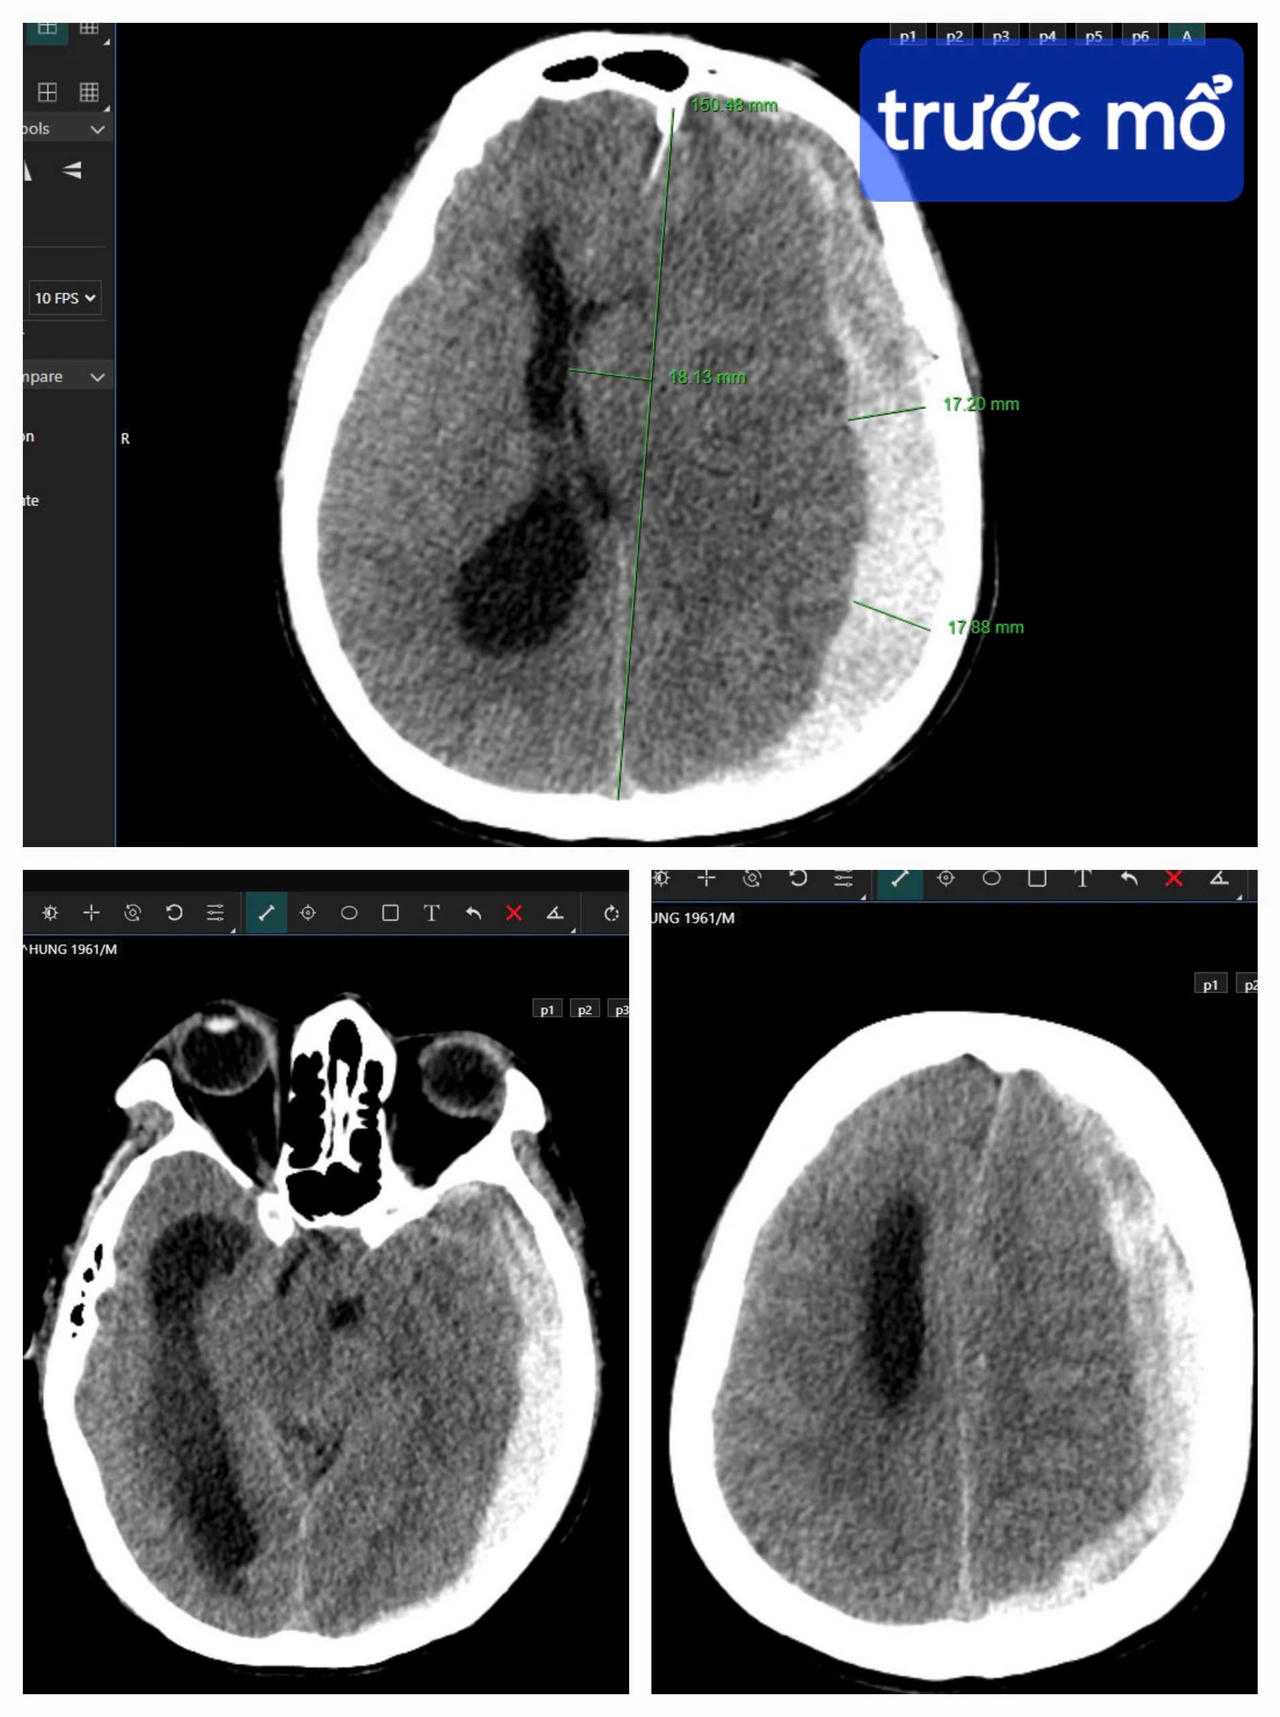

Kết quả chụp CT cho thấy bệnh nhân bị tụ máu dưới màng cứng bán cầu não trái, thoát vị qua liềm đại não sang phải. |

Trong tình huống khẩn cấp này, sự sống của bệnh nhân rất mong manh, bị tụ máu dưới màng cứng bán cầu não trái, thoát vị qua liềm đại não sang phải, bác sĩ phải chạy đua cùng thời gian, giành lại sự sống cho bệnh nhân từ tay “tử thần”.